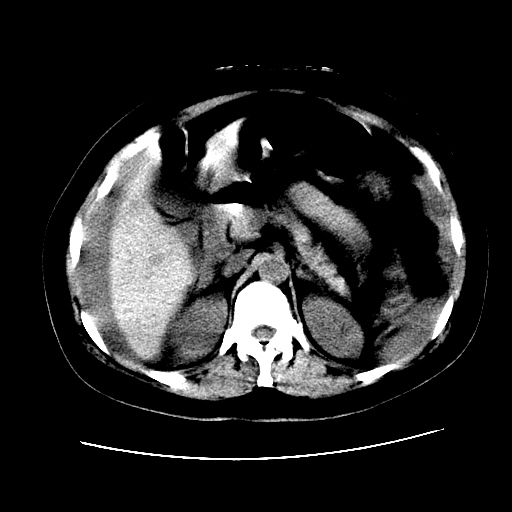

f,45y.怀孕4月晕倒,b超提示死胎,有手术结果,请展开讨论后明天告诉。

膈下-肠间隙内见气体密度影,子宫轮廓显示不清,宫腔-腹腔积液,首选考虑---子宫破裂出血。

1)宫腔妊娠。2)子宫破裂出血,腹腔及盆腔积血。

感谢同行们的高见。手术结果:子宫破裂出血。

我们的诊断是:腹、盆腔积液(考虑腹盆腔脏器破裂出血);宫腔妊娠。让人纳闷的是当时我们没有经验,现在回头看看分析:4月宫腔妊娠:1、洋膜囊不可能紧贴胎体这么小;2仔细看看子宫后壁肌层模糊不清;3腹、盆腔液体来源原因?4、45岁高龄妊娠有晕倒。由此可大胆诊断:宫腔妊娠子宫破裂出血。